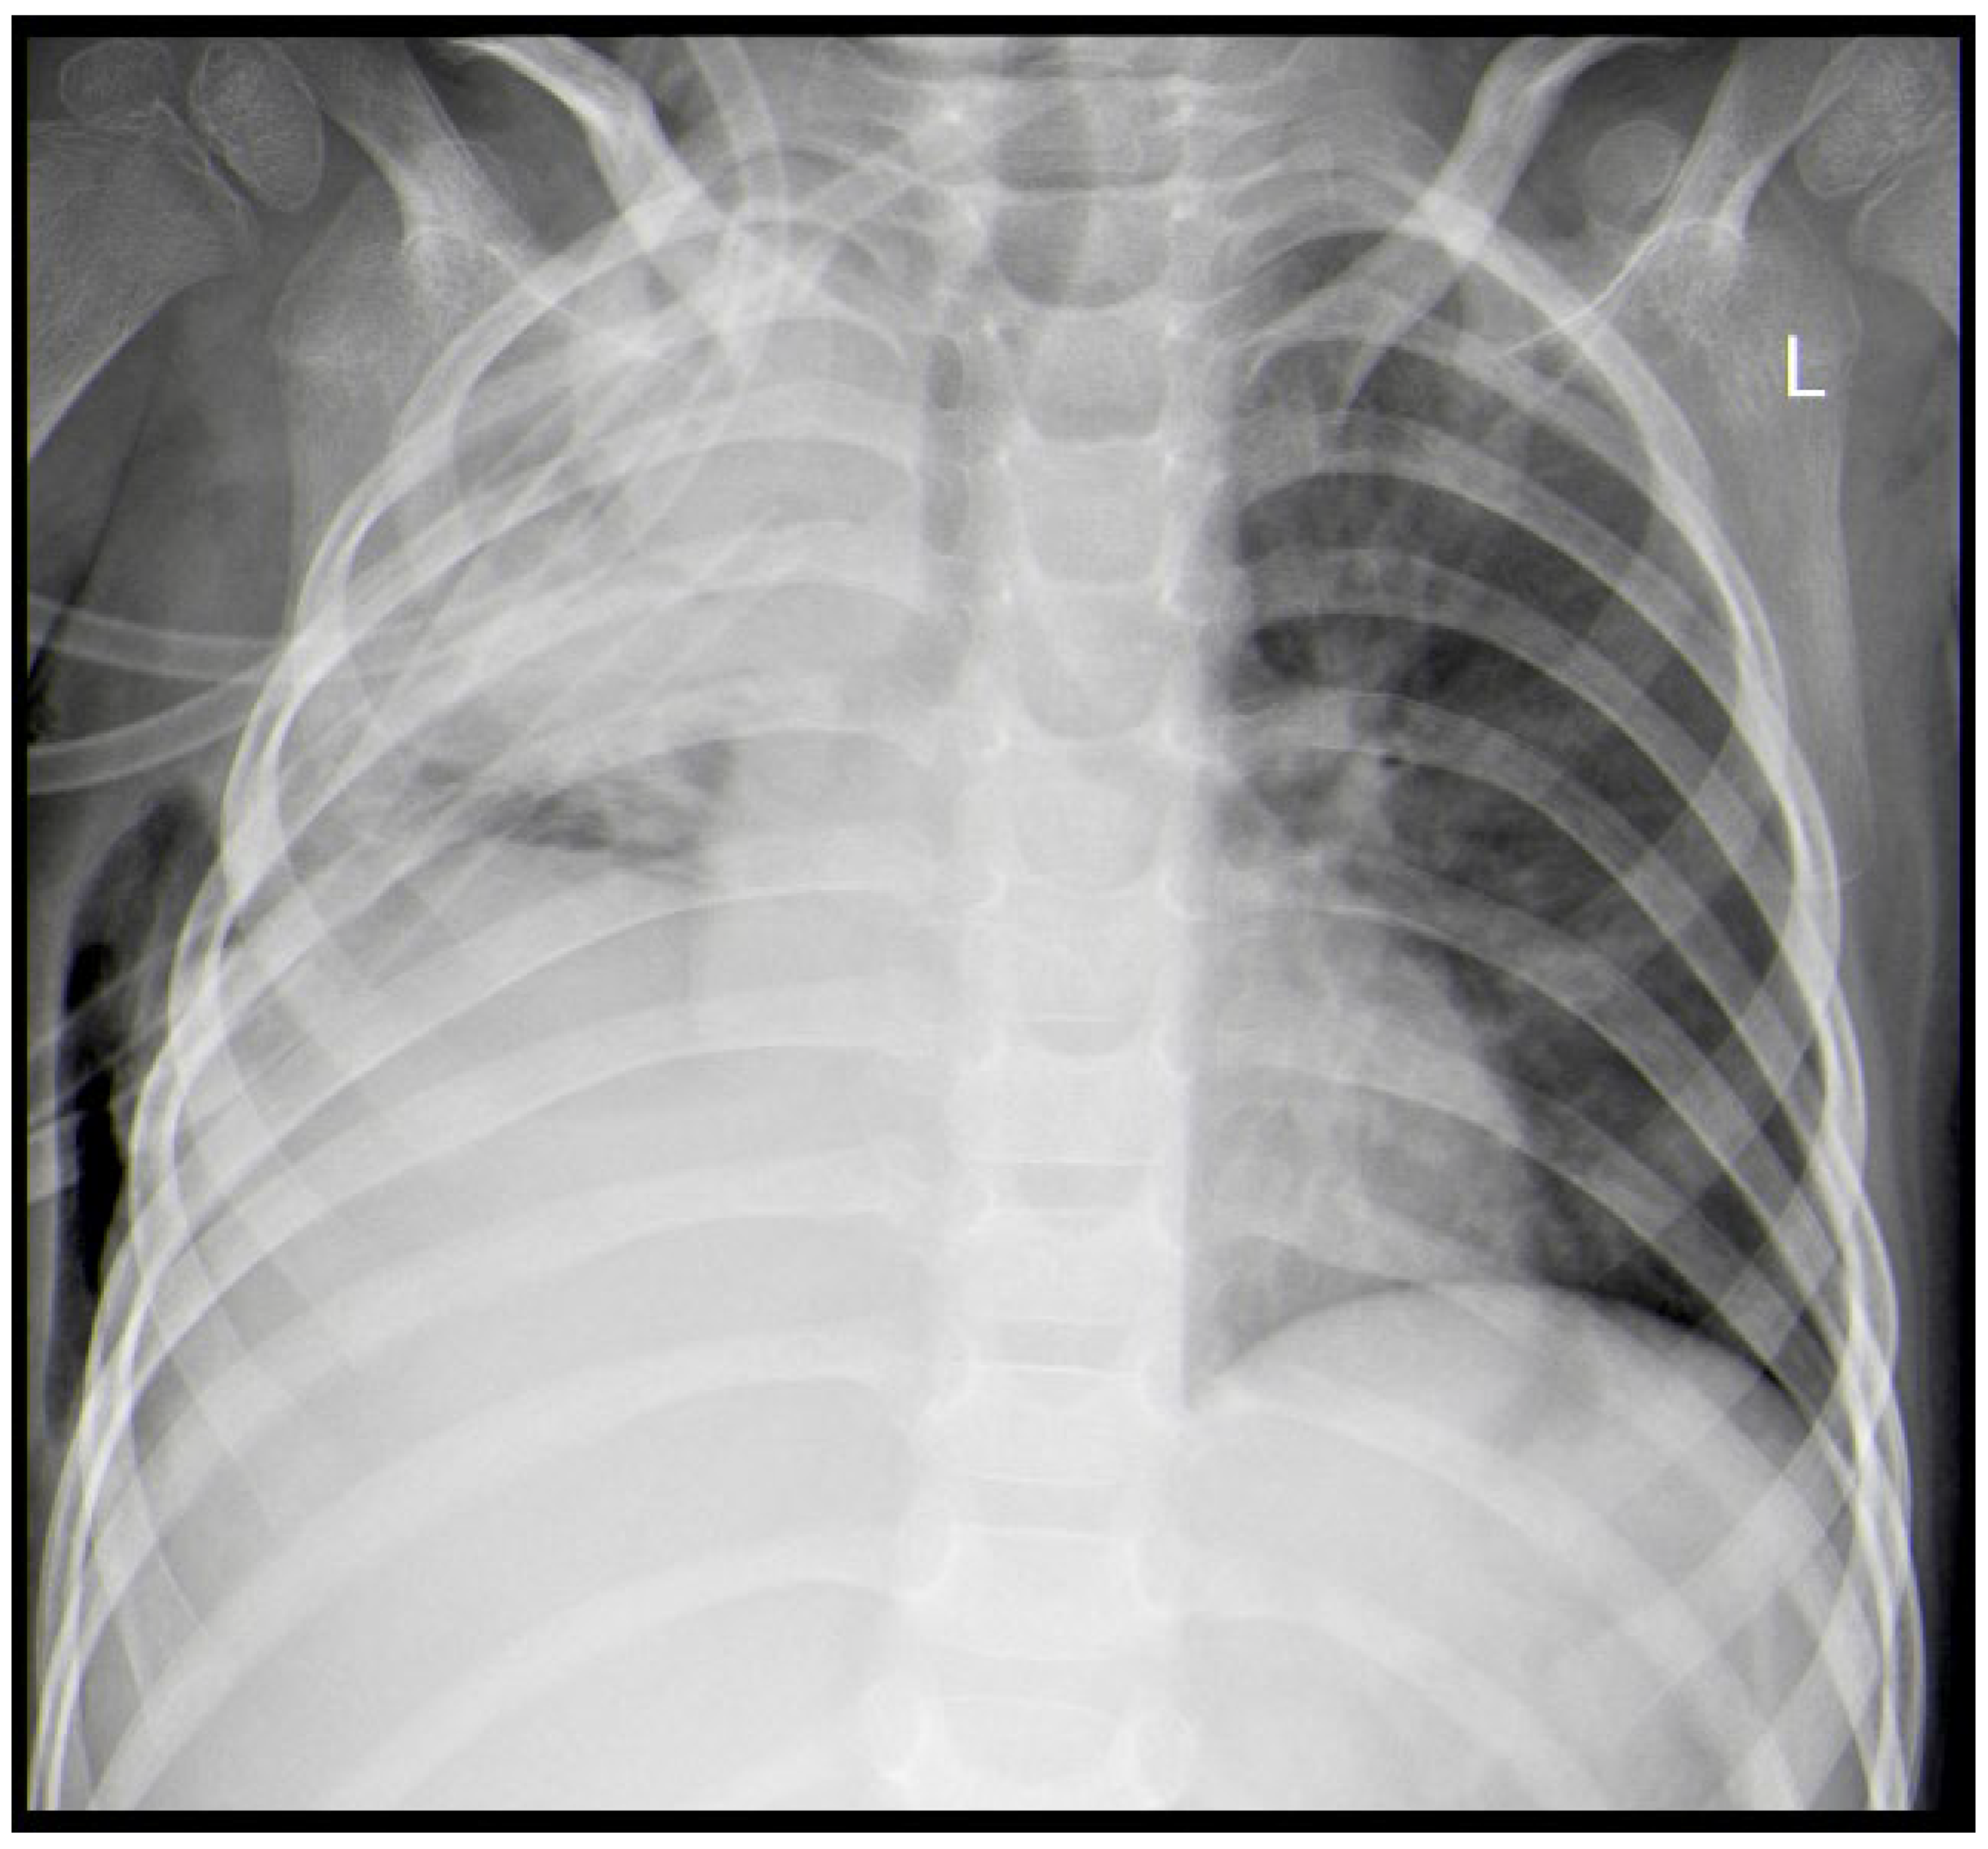

A Rare Case of Rhizomucor pusillus Infection in a 3-Year-Old Child with Acute Lymphoblastic Leukemia, Presenting with Lung and Brain Abscesses—Case Report

2. Case Report

Pahnev, Y.; Avramova, B.; Gabrovska, N.; Dontcheva, Y.; Tacheva, G.; Minkin, K.; Kreipe, H.; Yurukova, N.; Penkov, M.; Kartulev, N.; et al. A Rare Case of Rhizomucor pusillus Infection in a 3-Year-Old Child with Acute Lymphoblastic Leukemia, Presenting with Lung and Brain Abscesses—Case Report. Infect. Dis. Rep. 2026, 18, 2. https://doi.org/10.3390/idr18010002